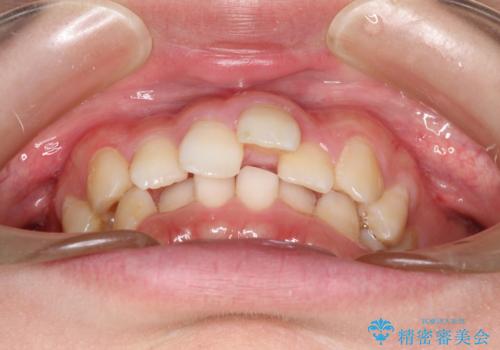

重度のガタガタのインビザラインによる非抜歯矯正

- 全体的なガタガタを気にされて来院されました。

抜歯矯正も考えられる状態でしたが、ご本人的になるべく歯を抜かない矯正を希望されました。

奥歯を後方に移動させるのと、歯と歯の間にわずかに隙間を作ることでスペースを確保して、抜歯をせず歯を並べる計画としました。

ガタガタの度合いが大きかったので少し時間がかかりましたが、非常に協力的な患者様でしたので、抜歯をせず計画通りに治療を終えることができました。